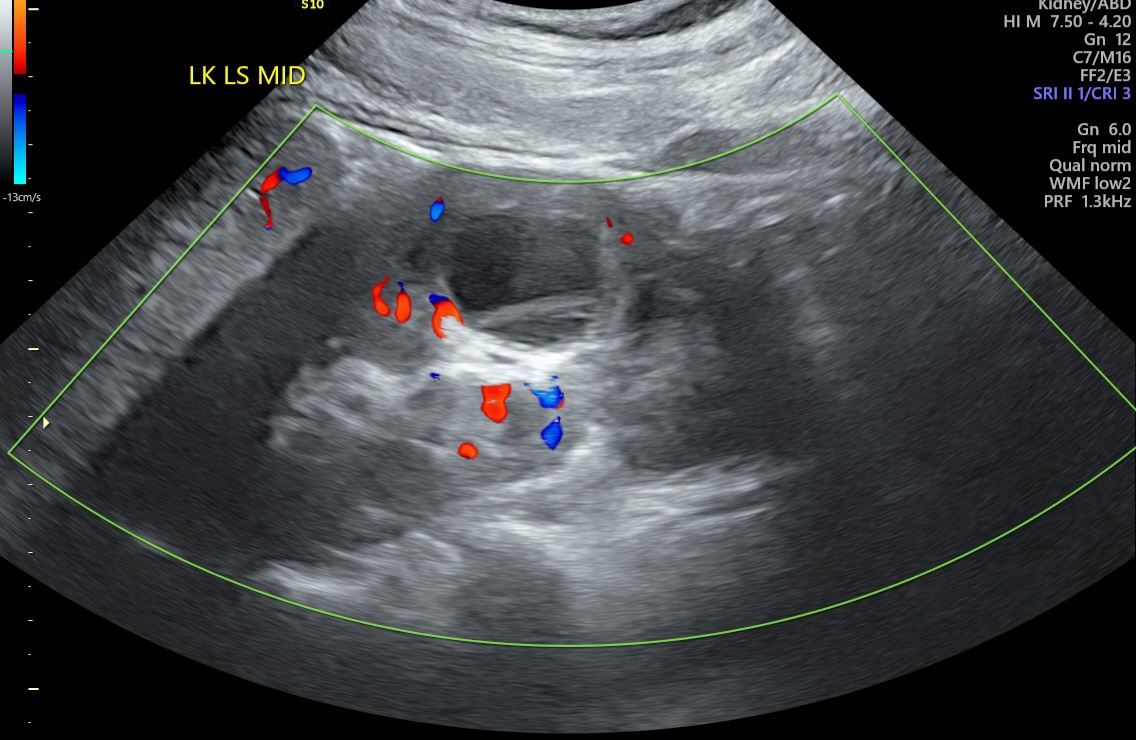

Czy mógłby ktoś mi powiedzieć czy 'infekcja cysty' to poprawna interpretacja załączonego USG?

Załączniki